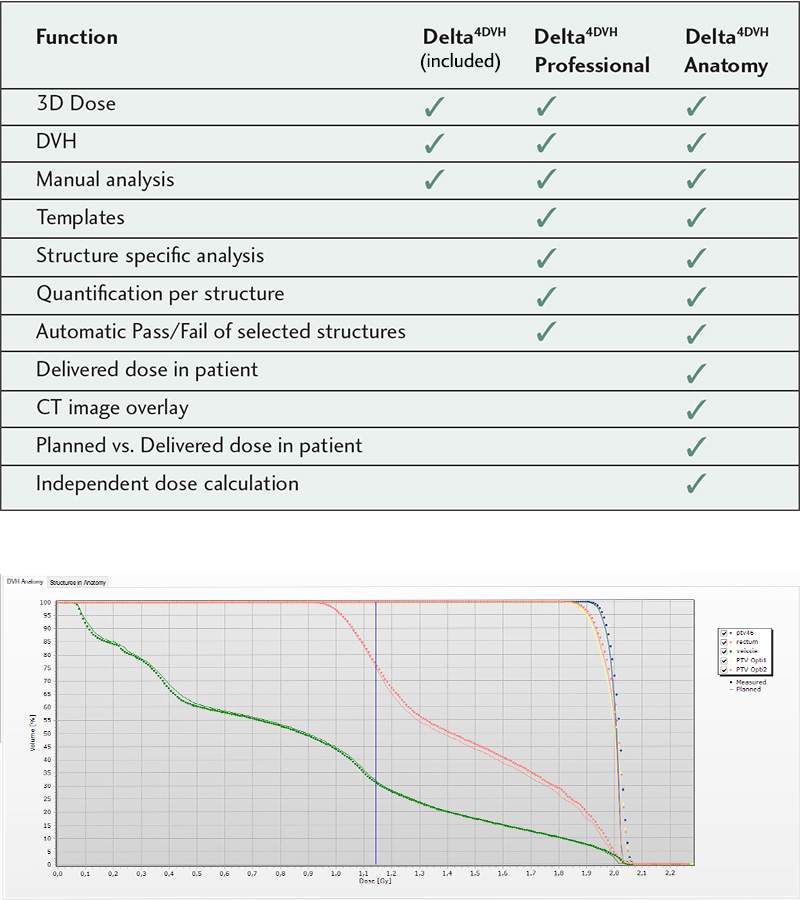

With the Delta4DVH Anatomy software option, you can verify and analyze the dose that has been delivered to the patient anatomy. Based on the measurements in the isocentric target region and dose calculation of the dose in the patient anatomy you now have a truly independent verification of the delivered dose.

Delta4 DVH Anatomy